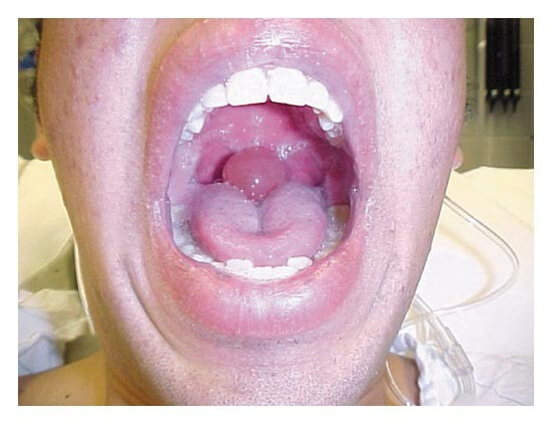

Quincke Edema

Signs and symptoms in patients with Quincke’s angioedema may include the following: Swelling of the face (eyelids, lips), tongue, hands, and feet. Throat tightness, voice changes, and breathing trouble and most concerning a swollen uvula. While rare, this can prevent the patient from breathing and is considered dangerous.

- Swollen tongue, throat & trouble swallowing